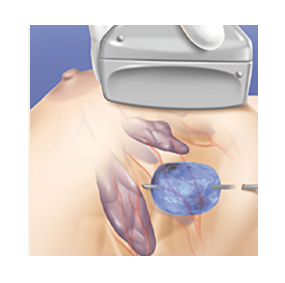

PROCEDURE DIAGRAM

Ultrasound imaging is used to locate the lesion. The breast is prepared and local anesthesia is given

A 3mm incision (about 1/8 inch) is made in a cosmetically and technically appropriate location

Using ultrasound guidance, a visica cryoprobe is positioned in the center of the lesion

The cycle is activated and an iceball forms around the tumor. The freezing temperatures destroy the tumor tissue